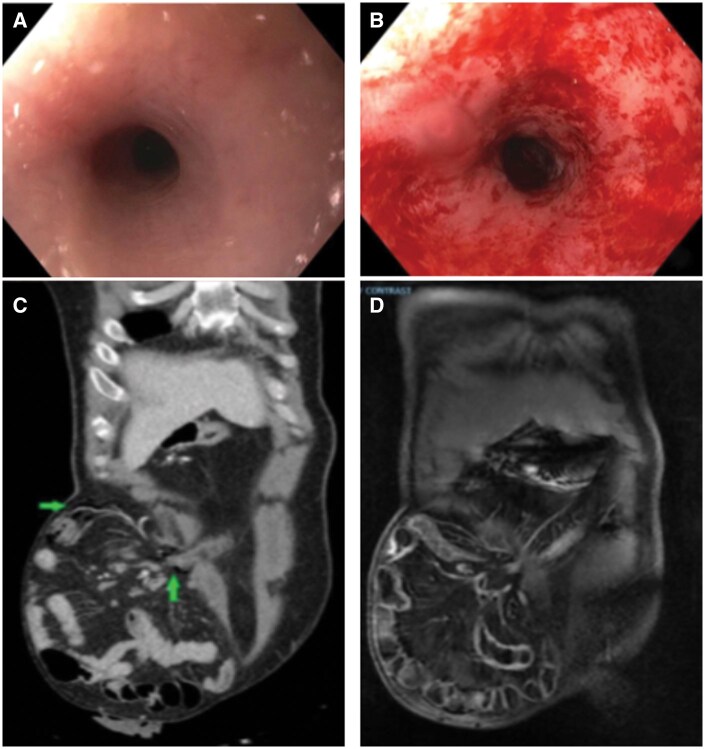

内镜下转移结肠气体泄漏模拟穿孔。

Endoscopic gas leak in diverted colon mimics perforation.